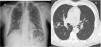

A 59-year-old male, with no toxic habits or history of lung disease, with a sister who died at 23 years of age due to CF. In the presence of non-specific febrile symptoms, a chest X-ray was requested, which revealed a pseudonodular infiltrate in the right upper lobe (RUL). Chest CT reported pulmonary nodule in RUL with adjacent nodules and centrolobular pulmonary micronodules (Fig. 1).